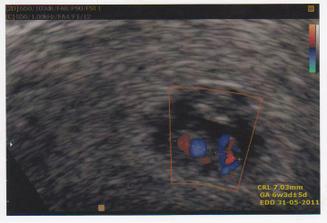

Taááákže 2. KET při 3. IVF